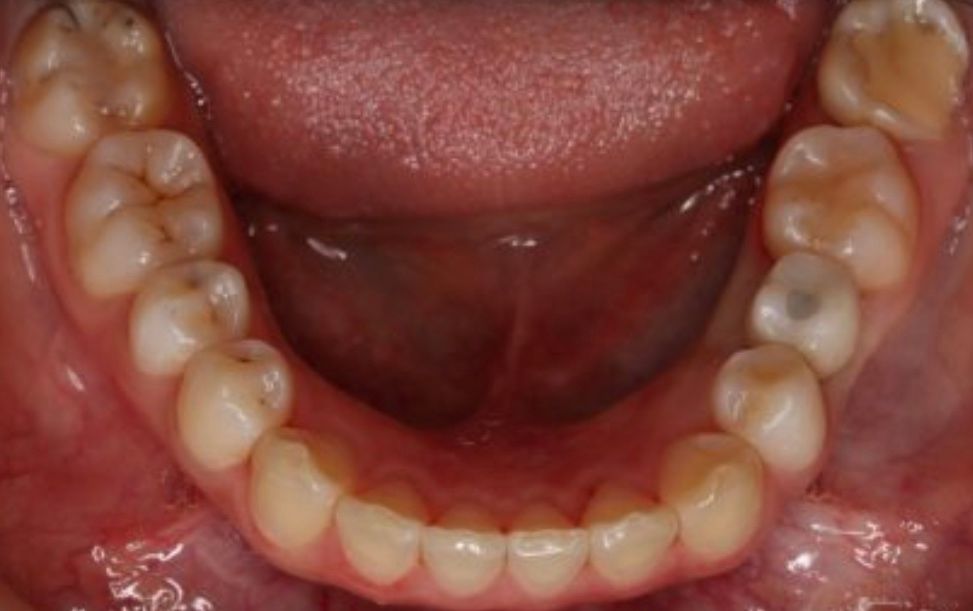

Fotos y videos